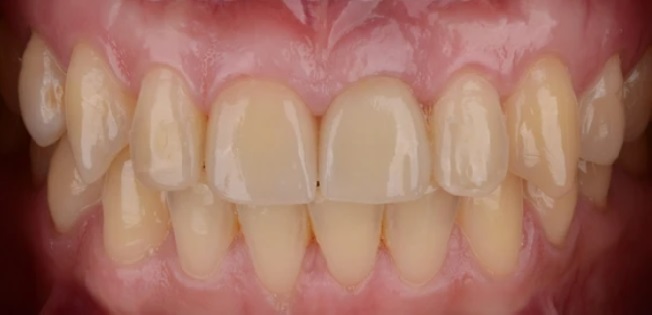

Проблема

Пациент обратился в клинику с проблемой отсутствия переднего зуба в следствии полученной травмы.

Решение

Пациенту проведено комплексное лечение по поводу восстановления переднего зуба при помощи имплантата Super Line и цельнокерамической коронки.